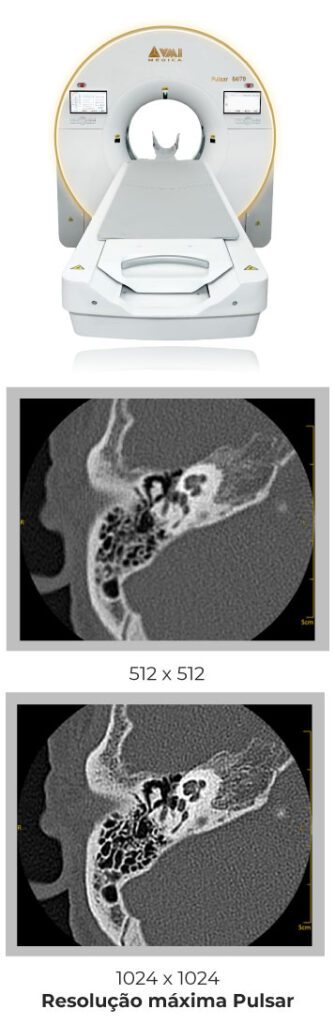

A linha Pulsar de tomografia computadorizada redefine a tecnologia no diagnóstico por imagem ao combinar inteligência artificial e engenharia de precisão.

Imagens mais nítidas

Alta performance para cenários que exigem máxima definição e produtividade. O Pulsar 128 une tecnologia avançada, velocidade de aquisição e excelência em imagem, com opções de abertura que ampliam o conforto e tornam o exame mais acessível a diferentes perfis de pacientes.